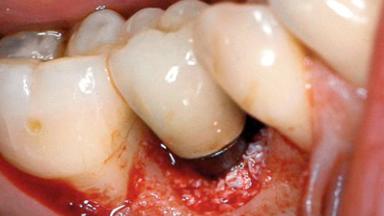

A 30-year-old female patient was referred to the Department of Periodontology of the University of Bern, Switzerland, by a dentist in private practice. Tooth 45 had been congenitally missing and had been replaced with a titanium implant three years prior to the first visit at the Department of Periodontology. The tissue level implant had a diameter of 4.1 mm, a length of 12 mm, and a sandblasted and acid-etched (SLA) surface (Straumann® Dental Implant System; Institut Straumann AG, Basel, Switzerland). The metal-ceramic crown on implant 45 had been cemented permanently. Implant 45 had been diagnosed with peri-implantitis by the referring dentist in the course of regular supportive care.

Peri-implantitis Modified by Submucosal Excess of Cement: Regenerative Peri-implantitis Therapy and Six-year Follow-up